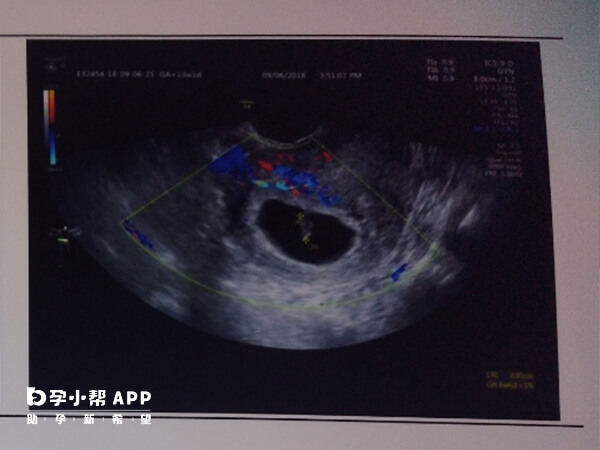

临床上,针对胎停以后孕囊送检一般有着较大的意义。这能够通过病理学检查,可确定胎儿停止发育的具体原因,如染色体异常、母体疾病等,这样可以方便医生针对性地制定治疗方案,同时如果胎停是自然淘汰的结果,那么还可以避免对患者进行不必要的治疗,减轻身心负担。

孕囊送检本身是一件作用非常大的检查,可以通过对孕囊的化验来排除一些导致胎停的原因,但是如果是第一次胎停育的话可以先观察一下,看是否还会出现同样的情况,如果再次出现胎停育的情况则可以对停育的胚胎进行化验。